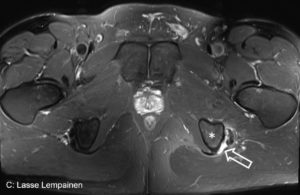

Figures 1-2. Complete proximal biceps femoris and semitendinosus rupture at the left side.

In an athlete a proximal one tendon avulsion with clear retraction should be treated surgically regardless of the hamstring tendon (BF, SM or ST). If two or all three of the hamstring muscles are avulsed surgery should be considered in all patients if there are not major contraindications to surgery. Suture anchors are typically used to reattach the tendon to bone (Figures 1 and 2).